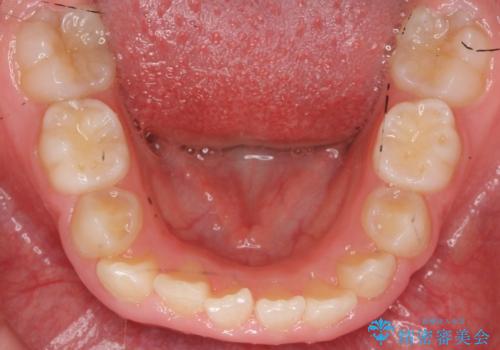

八重歯 歯を抜かずにインビザラインで

- 八重歯を主訴に来院。

抜かずに歯を少し削って入れる方法で並べました。

乳歯が永久歯に生え変わるまで成長観察を続け、永久歯列になってから治療開始しています。